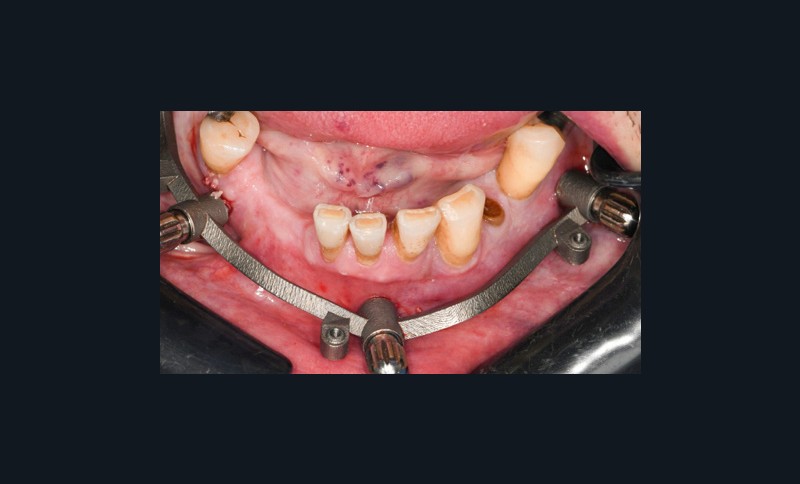

- appui dentaire : il est le plus fiable car son positionnement est permis grâce à des points fixes (fig. 4). Il reste bien sûr dépendant de la précision de l’alignement entre le STL de l’empreinte optique et le DICOM de l’examen CBCT ;

- appui muqueux : sa précision est inférieure. Réservé aux cas d’édentement total, il est conçu à partir d’un alignement avec une prothèse amovible complète comportant des marqueurs radio-opaques (fig. 5 à 8). Le risque d’imprécision est majoré par la dépressibilité de la muqueuse, la tuméfaction des tissus mous due à l’anesthésie, ou le positionnement initial en s’aidant de l’occlusion ;